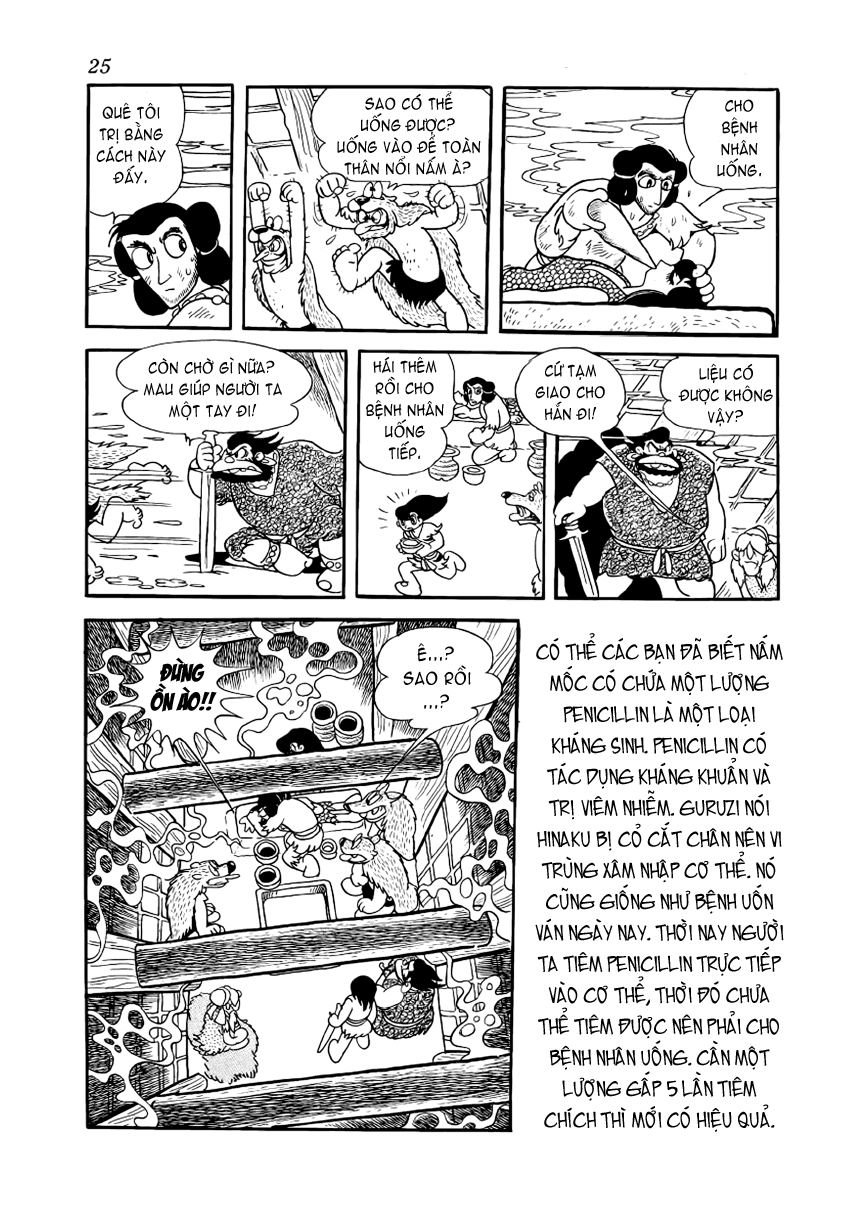

23-02-2017 17:05:45 GMT+7 20-12-2023 04:08:25 GMT+7Có một truyền thuyết cổ xưa về Hi no tori (Chim lửa), rằng bất kì ai uống máu loài chim này sẽ trở nên bất tử, đây là loài chim của thần thá Vì thế, những người vọng tưởng sự trường sinh bất lão luôn tìm kiếm và săn bắt loài chim ấy. Con chim lửa ấy bay mãi, nối liền từ quá khứ tới tương lai, nối liền những câu chuyện về ái hận sân si của những con người tưởng chừng như chẳng liên quan tới nhau, nhưng thật ra bản thể chỉ lại là một. Chim lửa , nó chết đi, rồi lại tái sinh trong tro tàn, sự tồn tại của nó là một vòng luân hồi bất tận. Sự tồn tại của con người và thế giới này cũng vậy, con người sinh ra, chết đi, và lại sinh ra ở một kiếp khác; thế giới diệt vong, rồi lại tái sinh; nghiệt này gieo xuống, nhân kia trả lại; và 12 câu chuyện trong Hi no tori cũng thế, tưởng như rời rạc nhưng thực ra lại kết lại thành một vòng tròn luân hồi… Và bắt đầu cho vòng tròn ấy là Bình minh, câu chuyện về tham vọng trường sinh bất tử của nữ vương Himiko.